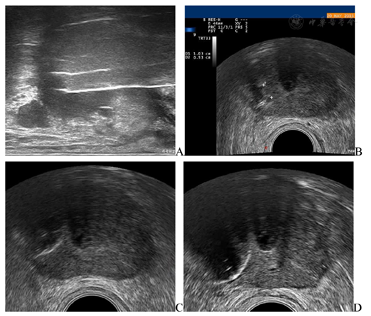

冷冻消融治疗(图3):患者全麻后取膀胱截石位,充分暴露会阴部,置入尿道保温装置。在经直肠超声引导下下先行前列腺右叶冷冻消融,超声仪器为Mylab Twice超声诊断仪(Esaote, Florence, Italy),TRT33双平面探头;冷冻仪器采用Endocare CryoCare CS冷冻仪(Varian Medical Systems, USA),3.0 cm V-Probe冷冻刀。经直肠超声引导下经会阴将冷冻刀分别穿刺置入前列腺右叶后外侧和前内侧,二根冷冻刀前后相距1 cm,左右相距0.5 cm;后外侧冷冻刀距直肠1.7 cm,前内侧冷冻刀距尿道1.6 cm。完成冷冻刀置入后,先开启前内侧冷冻刀按钮进行冷冻,待冰球出现后再开启后外侧冷冻刀按钮进行前列腺右叶冷冻消融术。先用80%冷冻功率冷冻4 min,温度降至-80 ℃,当冰球覆盖大部分右侧腺体,且与直肠距离为0.5 cm时,功率调低至60%,作为冷冻维持至10 min。然后进入复温模式,12 min后复温至4 ℃;然后再按上述操作流程进行第二循环冷冻治疗。